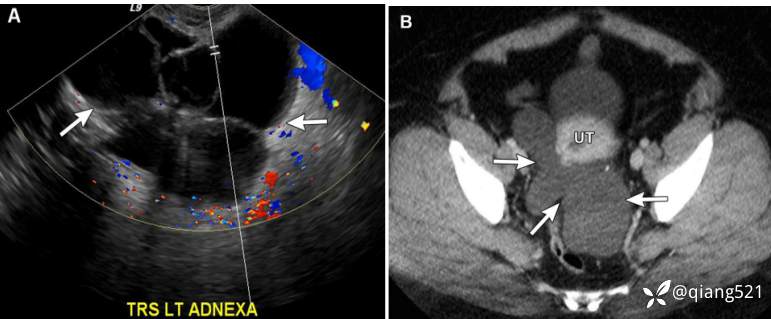

38 岁女性,患有腹膜包涵体囊肿。

经阴道盆腔超声彩色多普勒显示多房性无血管囊肿(箭头);卵巢与囊性结构相邻且分离。 B 轴向 CECT 显示骨盆中相应的分叶状液体密度结构(箭头)。盆腔抽吸显示单纯浆液。 UT,子宫。